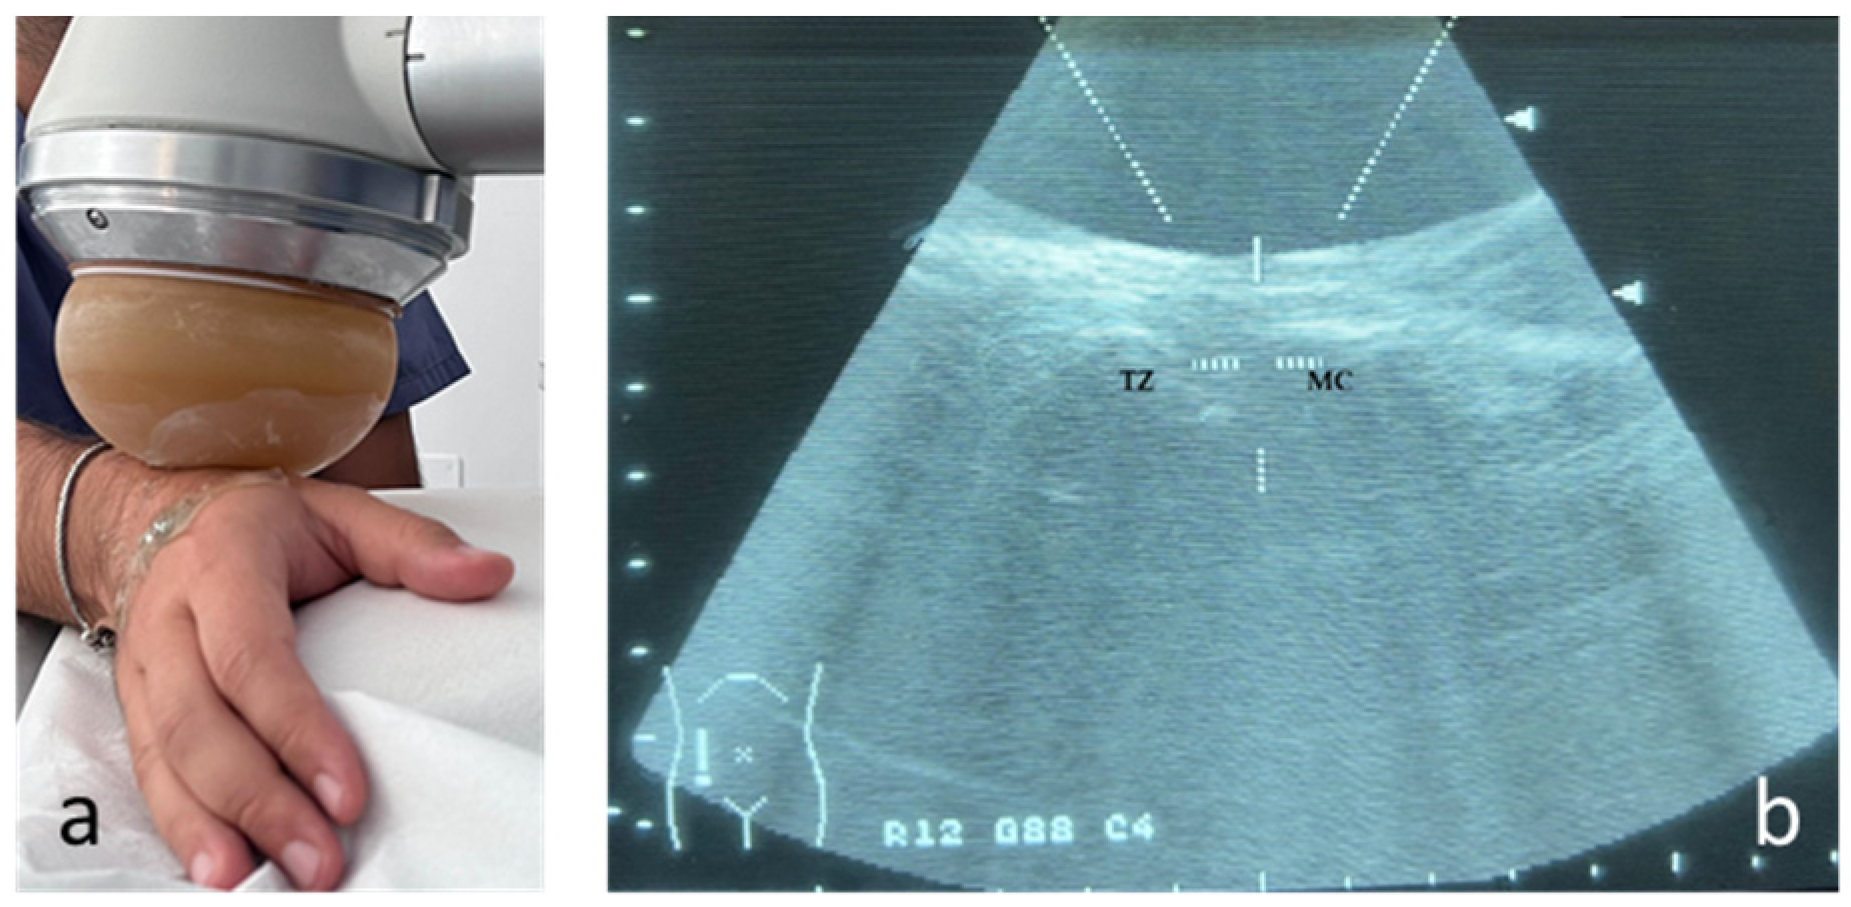

2.1. Shock Wave Group